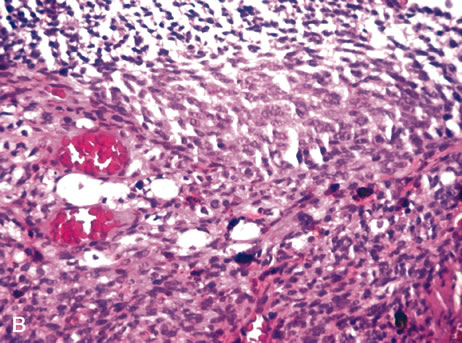

In 1931, Callender classified uveal melanomas based on cytologic features.166 He described six groups, four of which were based on cytology and two on other histologic features. The groups based on cytology were tumors composed of (1) spindle-A cells, (2) spindle-B cells (Fig. 26), (3) epithelioid cells (Fig. 27), (4) a mixture of epithelioid and spindle cells (Fig. 28). The fifth group consisted of tumors with a fascicular pattern, and the the sixth group was composed of tumors that could not be classified in the other groups because of extensive necrosis (Fig. 29). Spindle cells are described as fusiform and arranged in tightly cohesive bundles. The plasma membranes of the cells are indistinct and have a syncytial appearance. Spindle-A cells have a slender nucleus with fine chromatin and a longitudinal fold in the nuclear envelope that gives the appearance of a line. Spindle-B cells have a slightly plumper nucleus, coarser chromatin, and a more prominent and eosinophillic nucleolus. Epithelioid cells are larger and more pleomorphic. They have an abundant glassy cytoplasm, a polyhedral shape, and a distinct cell border and are less cohesive. Epothelioid cells tend to have a larger and rounder nucleus than the other types, with a more angular nuclear envelope and irregular indentations. The chromatin is coarse and marginated, and large eosinophillic nucleoli are present.

Fig. 26. Choroidal melanoma. Note spindle-B melanoma cells with nucleoli. (Hemotoxylin-eosin ×160.)

Fig. 27. Choroidal melanoma. The epithelioid melanoma cells show large nuclei and prominent nucleoli. (Hemotoxylin-eosin ×160.)

Fig. 28. Choroidal melanoma. The tumor shows a mixture of spindle cells and epithelioid cells. Both spindle A and spindle B cells are present. (Hemotoxylin-eosin ×160.)

Fig. 29. Choroidal melanoma. Necrotic tumor cells are mixed with melanophages. (Hemotoxylin-eosin ×200.)